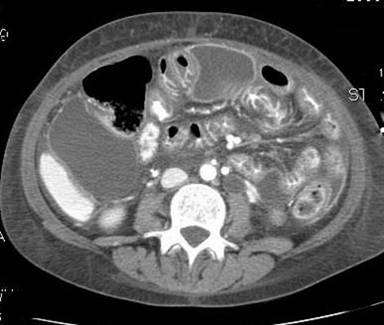

A complete blood count revealed a hemoglobin of 10.1 g/dL (reference range: 11.7-15.5), while the white blood cell count and differential and the platelet count, serum glucose, electrolytes, including serum bicarbonate, renal function (blood urea nitrogen 5 mg/dL, reference range: 7-20 mg/dL; creatinine 0.7 mg/dL reference range: 0.5-1.2 mg/dL) and urine output were all normal. Lactic acid levels were elevated at 8.5 mmol/L (reference range: 0.3-1.3 mmol/L). Spot urine for ketones was negative. Liver panel showed - alanine aminotransferase (ALT, 34 U/L; reference range: 3-45 U/L), aspartate aminotransferase (AST, 35 U/L; reference range: 3-35 U/L), alkaline phosphatase (131 U/L; reference range: 44-160 U/L), total bilirubin (1.6 mg/dL; reference range: 0.2-1.0 mg/dL), direct bilirubin (0.3 mg/dL; reference range: 0-0.3 mg/dL) - was unremarkable, as were the serum amylase (11 U/L; reference range: 28-100 U/L) and lipase (<10 U/L; reference range: 10-300 U/L). Serum albumin was low (1.6 g/dL; reference range: 3.5-5.5 g/dL) and international normalized ratio was mildly elevated (1.5; reference range: 0.9-1.1). A creatine kinase level (42 U/L; reference range: 10-160 U/L) and echocardiogram were normal. Serum and urine toxicology screening was negative. Her ammonia levels were elevated at 146 μg/dL (reference range: 15-45 μg/dL). Computerized tomography (CT) imaging of the abdomen showed multiple loculated fluid collections in the sub hepatic space measuring 8.6x5.0 cm extending into the paracolic gutter. There was also a rim-enhanced collection anterior to the rectum measuring 7.4x4.0 cm (Figure 1). Several other rim-enhancing collections were identified within the anterior abdomen and within the left paracolic region. It also showed diffuse bowel wall thickening involving small bowel and left colon. There was also diffuse low hepatic attenuation in the liver suggestive of fatty change. The patient underwent percutaneous drainage of two of the loculated fluid collections with aspiration of 700 mL of murky brown fluid and placement of 10-F locking pigtail catheters. The patient continued to deteriorate with worsening hypoxia and was intubated and was taken to the operating room for an exploratory laparotomy. There was no evidence of any necrosis or tissue ischemia around the jejunostomy tube and the rest of the small bowel and stomach appeared normal. The liver was noted to be yellowish orange and a wedge biopsy of the liver was obtained. There was no remaining fluid collection around the percutaneous drainage catheter. A small amount of purulent fluid from the pelvis was aspirated and was sent for culture and a Jackson-Pratt drain was placed into the fluid collection. Fluid cultures grew Escherichia coli and the patient was started on ceftriaxone. Blood cultures were negative. Repeat CT abdomen imaging showed residual small loculated collections along the left paracolic gutter and a percutaneous, 10-F locking pigtail catheter into a left paracolic gutter abscess was placed by interventional radiology.

Figure 1. CT abdomen showing multiple loculated fluid collections in the sub hepatic space. |